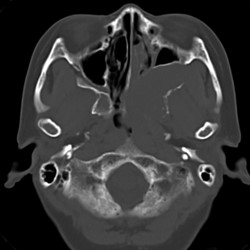

CT

腫瘤は筋より軽度低吸収である。腫瘤による骨破壊があるが、左翼口蓋窩の高度拡大や左上顎洞・左篩骨洞壁の変形など腫瘤による長期間に及ぶ圧排性変形を疑う骨変形がある。腫瘤の一部に石灰化があるが、破壊された骨の取り残しの可能性もある。